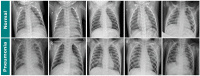

Pneumonia is responsible for high infant morbidity and mortality. This disease affects the small air sacs (alveoli) in the lung and requires prompt diagnosis and appropriate treatment. Chest X-rays are one of the most common tests used to detect pneumonia. In this work, we propose a real-time Internet of Things (IoT) system to detect pneumonia in chest X-ray images. The dataset used has 6000 chest X-ray images of children, and three medical specialists performed the validations. In this work, twelve different architectures of Convolutional Neural Networks (CNNs) trained on ImageNet were adapted to operate as the resource extractors. Subsequently, the CNNs were combined with consolidated learning methods, such as k-Nearest Neighbor (kNN), Naive Bayes, Random Forest, Multilayer Perceptron (MLP), and Support Vector Machine (SVM). The results showed that the VGG19 architecture with the SVM classifier using the RBF kernel was the best model to detect pneumonia in these chest radiographs. This combination reached 96.47%, 96.46%, and 96.46% for Accuracy, F1 score, and Precision values, respectively. Compared to other works in the literature, the proposed approach had better results for the metrics used. These results show that this approach for the detection of pneumonia in children using a real-time IoT system is efficient and is, therefore, a potential tool to aid in medical diagnoses. This approach will allow specialists to obtain faster and more accurate results and thus provide the appropriate treatment.